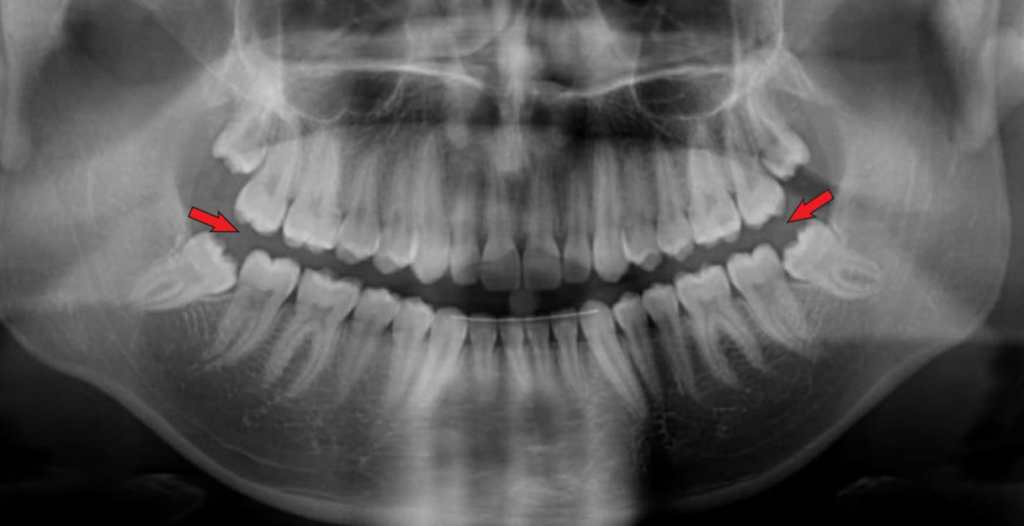

- Avaliar o posicionamento dos dentes sisos;

Bem como a presença de supranumerários, agenesias, posições pré-eruptivas, transposições e posições ectópicas, dentes retidos, cistos foliculares, malformações coronárias dos germes dentários, direção axial dos dentes, anatomia radicular e dilacerações.

Também pode verificar a presença de cáries e as condições das restaurações existentes e a natureza de alguns desvios da linha mediana.